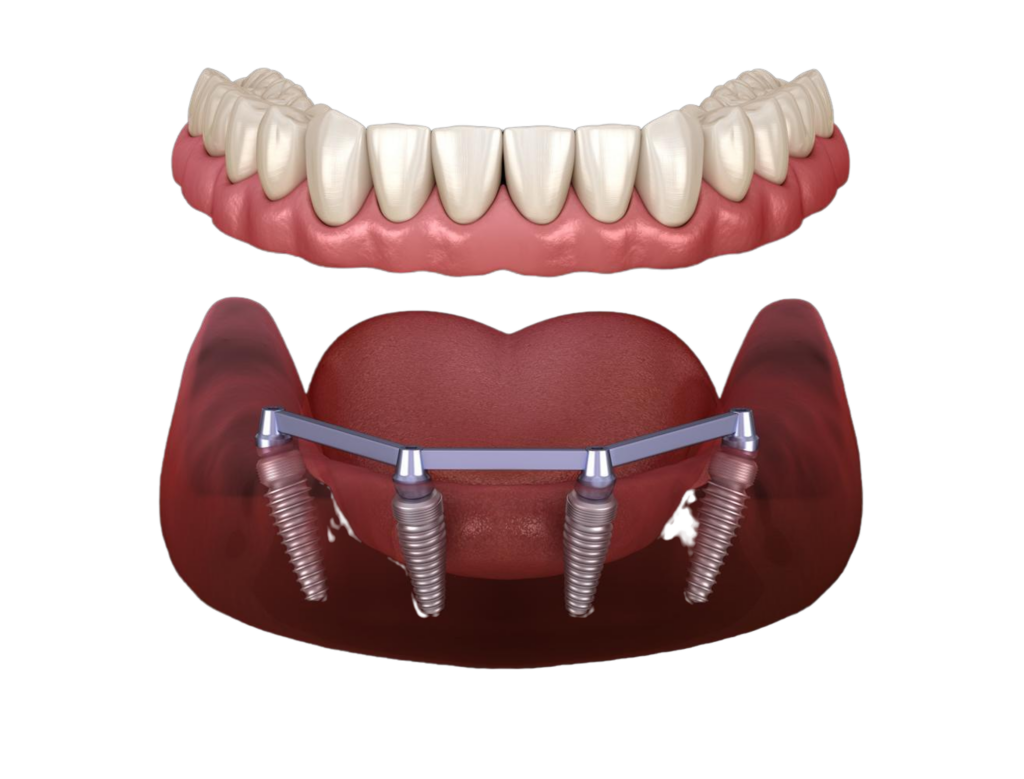

Full-mouth dental implants are a complete set of dental implants, typically between 6 and 12, placed in the upper and lower jaws. They serve as replacement teeth roots, providing a strong and stable base for permanent or removable replacement teeth.

Dental implants are anchored directly into the jawbone, unlike traditional dental bridges or dentures, which rest on top of the gums. This provides a more secure and natural feeling solution for those with missing or damaged teeth.